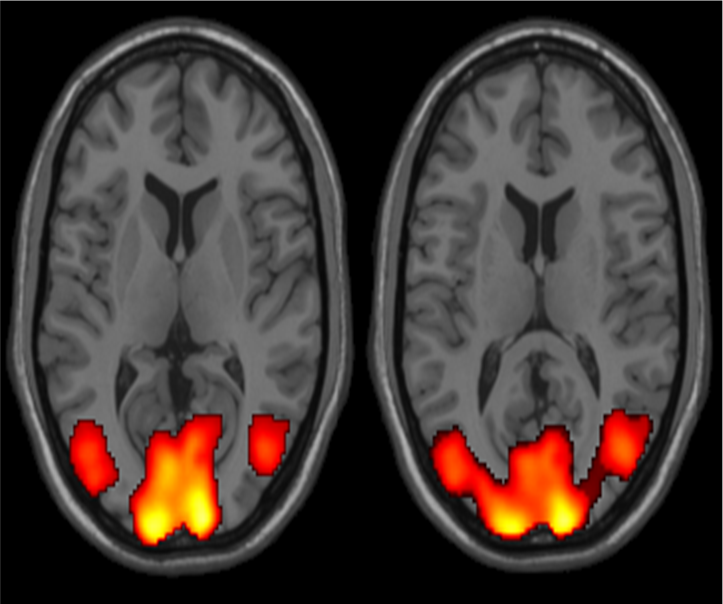

Activation after memory task In the way described above, the neural activity in a location can be measured. fMRI is very good at localizing the area compared to other techniques of brain imaging such as PET, SPECT or EEG, but it is not as good as EEG at identifying the timing of neural activity. fMRI relies on the idea that specific areas of the brain are called in as necessary to perform a cognitive task. It also relies on people consistently using those specific areas.